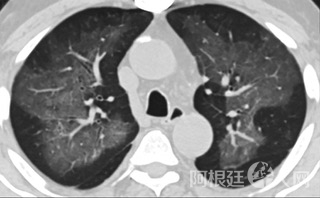

疑点一,电子烟患者的CT影像和临床表现并不具有特异性。所谓美国电子肺炎患者,其实是对没有其他合理诊断证据、吸食电子烟肺炎患者的统称。这些患者在病发前90天内吸食了电子烟,尤其值得注意的是,部分患者的CT影像特征和临床表现与病毒性肺炎患者极其相似。

中、下肺轴位CT平扫显示毛玻璃样混浊伴胸膜下保留。(同一病人CT影像)